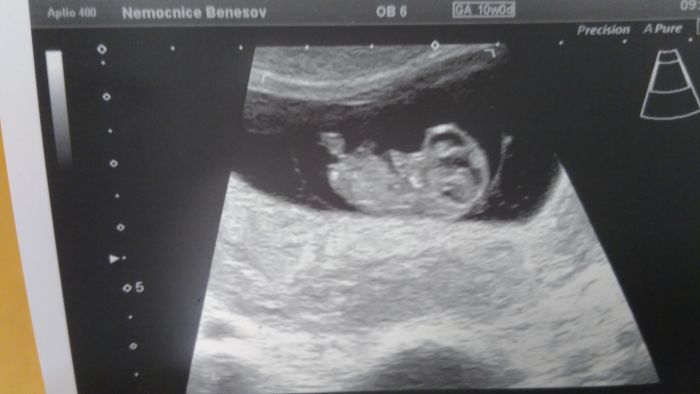

Ahoj holky, mate uz fotky z utz? Ja dnes byla na kontrole a mam radost, protoze i kdyz je mensi, nez by melo byt, tak roste a srdicko tluce :-) jinak podle utz jsem o tyden mene, nez podle ms, tedy 6+5 a prcek ma 7,5mm :-D I tak jsem uz dostala prukazku, coz me prekvapilo, ze tak brzy... Ohledne screeningu se me doktorka ani neptala, jestli chci a rovnou mi rekla, at prijdu 4.5. na testy a donesu si 1000Kc, ze mi to pak pojistovna vrati a 17.5. at prijdeme s manzelem na utz. Pry az tam se zjisti, zda je mimco opravdu v poradku. Uz aby to bylo, takhle mam z kazde kontroly nervy, zda je vse ok

Utz..ze 7tt..kvuli tomu zda bije srdicko..ted jdeme 12teho..uz se s tatkou tesime...dnesni krece nas oba vydesili..uz nejsem nejmladsi..?